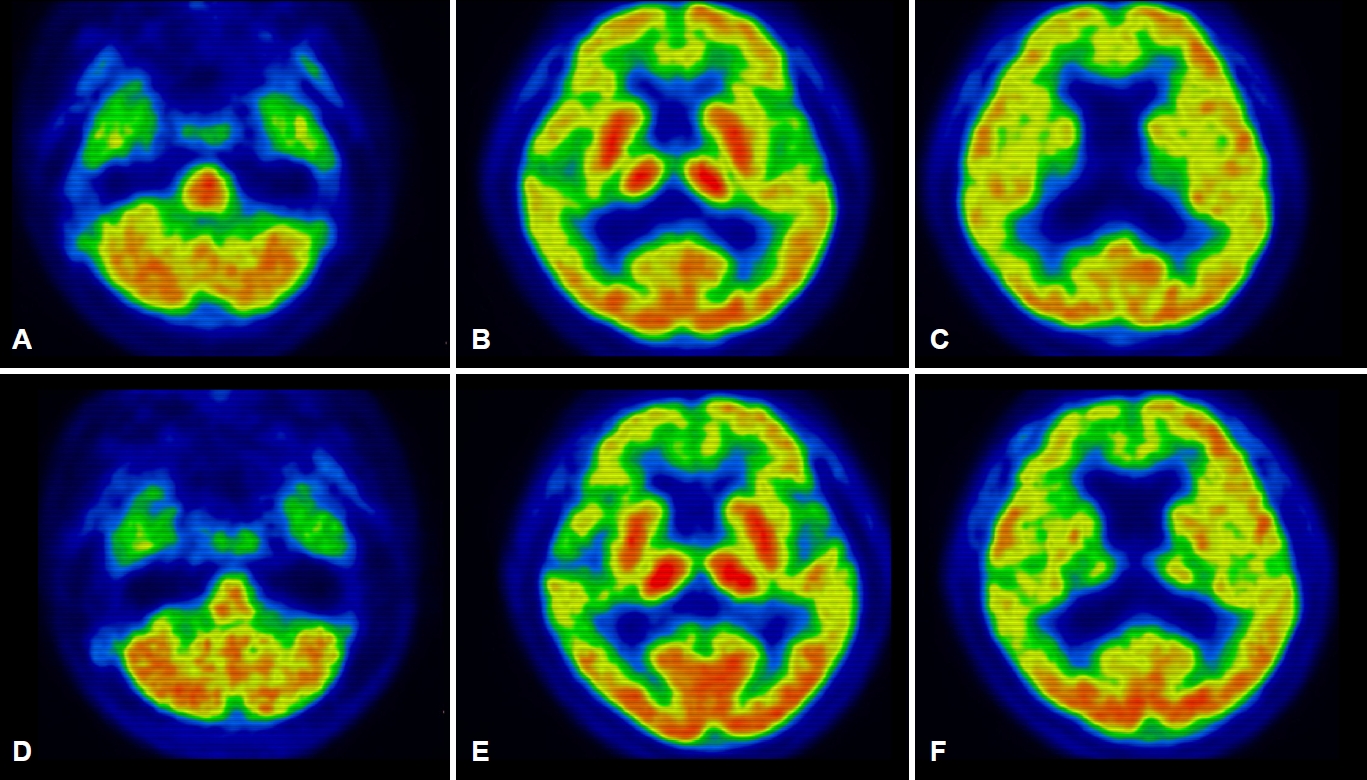

6년의 학력을 가진 오른손잡이인 61세 여자 환자가 서서히 시작된 기억력 및 언어능력저하로 지역 치매안심센터를 경유하여 2019년 6월 본원 신경과로 진료가 의뢰되었다. 한 달에 1-2번 정도 왕래하는 딸에 의하면, 환자는 약 1년 전부터 자신이 했던 일을 반복적으로 잊어버리는 경우가 많았고 물건의 위치를 기억하지 못하였다. 오래된 기억은 문제가 없었다. 그리고 대화할 때 단어를 쉽게 떠올리지 못하는 모습을 보였다. 길 찾기에는 문제가 없었고 성격 변화도 없었다. 집안 살림을 스스로 할 수 있었다. 과거병력과 치매 가족력에서 특이 소견은 없었다. 신경계진찰에서 운동, 감각 및 심부건반사는 정상이었다. 한국판간이정신상태검사(Korean-Mini Mental Status Examination, K-MMSE)는 17점, 임상치매평가척도(Clinical Dementia Rating, CDR)는 0.5점 그리고 임상 치매평가척도-총합점수(CDR-Sum of boxes, CDR-SB)는 1.5점이었다. 비문해노인특성반영 인지기능검사(Literacy Independent Cognitive Assessment)에서 나이와 학력에 비하여 기억력, 언어기능, 시공간기능, 집행기능 및 계산기능의 저하 소견이 관찰되었다. 뇌 자기공명영상(magnetic resonance imaging, MRI)에서는 전두측두엽과 해마의 위축이 관찰되었는데 우측에서 더 명확한 변화가 관찰되었다(Fig. 1-A-D). 18F-flutemetamol 아밀로이드양성자단층촬영(PET)도 시행되었다. 18F-flutemetamol 주입 10분 후에 얻은 초기 동적영상에서는 우측 전두측두두 정엽의 기능저하 소견이 관찰되었으나(Fig. 2-A-C) [4,5], 18F-flutemetamol 주입 90분 후 촬영한 지연 영상에서는 아밀로이드 침착이 보이지 않았다(Fig. 3-A-C; global standardized uptake value ratios, 1.33; cut-off value, 1.50). 뇌척수액에서 시행한 생물표지자 분석(INNOTEST ELISA kit; Fujirebio Diagnostics, Ghent, Belgium)에서 Aβ42 385 pg/mL (cut off value, 481 pg/mL), 총 타우(total tau) 524 pg/mL (cut off value, 326 pg/mL), p타우(p-tau)181 68 pg/mL (cut off value, 57 pg/mL)의 결과를 얻었다[6]. 뇌 PET검사에서 아밀로이드 축적을 보이지 않았으나, 환자의 임상 양상, 신경심리검사, 뇌 MRI, PET 초기 동적영상 및 뇌척수액생물표지자검사 결과를 종합할 때, 환자는 아밀로이드 양성, 타우 양성 및 신경변성 양성 상태의 조기발병 기억상실다중영역경도인지장애로 진단하였다. 환자는 검사 이후 1년 사이에 인지기능과 일상활동의 급격한 악화를 보였다. 환자는 전날 외식한 것을 기억하지 못하였다. 오후 3시에 남편에게 저녁을 먹으라고 차리기도 하였으며, 세탁한 것과 그렇지 않은 것을 구분하지 못하였다. 전혀 의사소통이 되지 않고 엉뚱한 행동을 하였다. 말을 할 때도 더듬거리면서 단어를 잘 말하지 못하였고 말수가 점차 줄어들었다. 집 근처에서조차도 방향을 헷갈려 하고 집안에서도 길을 헤매게 되었다. 금전 및 은행 업무는 전혀 할 수 없었다. 원래는 사교적인 성격이었으나 전혀 모임에 나가지 않았고 남편이 외출하면 불안해하였다. 반찬도 잘 못하고 하더라도 양이나 간 조절이 안되었다. 2020년 7월에 시행한 신경계진찰에서 운동, 감각 및 심부건반사는 정상이었다. K-MMSE는 13점, CDR은 2점, CDR-SB는 10점이었다. 뇌 MRI에서는 1년 전에 보이던 뇌위축이 더 진행된 소견을 보였다(Fig. 1-E-H). 18F-flutemetamol 아밀로이드 PET검사상, 초기 동적영상에서는 우측 전두엽과 양측 측두두정엽의 기능저하 소견이 관찰되었으나(Fig. 2-D-F), 지연영상에서는 여전히 아밀로이드 침착이 보이지 않았다(Fig. 3-D-F; global standardized uptake value ratios, 1.22). 환자는 이후로도 점차 악화되는 경과를 보여 2021년 4월에 시행한 검사에서는 K-MMSE 10점, CDR 2점, CDR-SB 11점을 기록하였다. 환자의 아포지단백질E (apolipoprotein E) 유전자아형은 ε4/ε4였다. 가족력은 없었지만 조기발병 치매 환자에서 비전형적인 알츠하이머치매의 생물표지자 발현을 보여 시행한 유전자검사(targeted exome sequencing; Dxome, Seongnam, Korea)에서 아밀로이드전구단백질(amyloid precursor protein, APP), 프레세닐린-1 (presenilin [PS]-1) 그리고 프레세닐린 -2 (PS-2)에는 원인 유전자변이(causative gene mutation)가 없음을 확인하였다.

61세 여자 환자는 3년여에 걸쳐 기억장애를 포함한 여러 영역의 인지장애와 이로 인한 일상활동장애를 보였으며, 증상이 서서히 발생하여 지속해서 악화하였다. 뇌 MRI에서의 우측 전두측두엽의 뇌위축과 아밀로이드PET의 조기 동적영상에서 전두측두두정엽의 대사 저하 양상이 관찰되는 것은 감별진단으로 알츠하이머치매 외에 전두측두치매나 피질기저핵변성도 고려할 수 있다. 그러나 3년간의 임상 경과로 미루어 환자는 초기에 현저한 기억저하를 보였고, 두드러진 이상행동을 보이지 않았으며 운동질환과 관련된 신경계 이상을 보이지 않아 전두측두치매나 피질기저핵변성보다는 알츠하이머치매가 보다 적합한 임상진단명으로 생각되었다. 뇌척수액 검사에서는 Aβ42 감소, 총 타우 증가, p-tau181 증가가 관찰되어 알츠하이머병 병태생리 과정에 대한 증거가 생물표지자로 일치하는 소견이었으나 아밀로이드PET에서 음성이 관찰되었다. 환자는 PET-/CSF+ 알츠하이머치매의 가능성을 가장 높게 생각하였으나 1년 후 중기 치매 진행된 상태에서도 아밀로이드PET 결과가 여전히 음성으로 관찰되어 환자의 최종적인 진단명이 알츠하이머병인지 또는 알츠하이머병 외에 다른 병이 동반되어 있는지에 대해서는 뇌의 병리조직검사 결과가 뒷받침되어야 하는 제한점을 가진 증례이다.

2011년 NIA-AA 진단기준이나 2018년의 아밀로이드병증, 병적 타우 및 신경퇴행을 포함하는 ATN 분류체계 연구 진단기준[7]에서 제시한 아밀로이드병증을 확인하기 위한 생물표지자는 뇌척수액 Aβ42 또는 Aβ42/Aβ40 감소 혹은 아밀로이드PET 양성을 포함한다. 아밀로이드PET의 아밀로이드 축적 정도와 뇌척수액 Aβ42는 높은 수준의 음의 상관관계를 보이는 것으로 알려져 있으므로, 한국의 임상 현장에서는 두 검사 모두를 시행하기보다는 접근성이 좋은 아밀로이드PET가 주로 선택된다. 그러나 본 증례와 같이 PET-/CSF+ 알츠하이머치매 생물표지자를 가지는 예들이 치매 환자의 5%나 치매 전단계에서는 20% 정도까지 이르는 것으로 보고되었다. PET-/CSF+와 같이 생물표지자 결과의 불일치는 먼저 각 생물표지자가 반영하는 아밀로이드 단백질의 종류가 다른 것과 연관있을 수 있다. 대부분의 효소결압면역흡착층정 검사 도구(ELISA kit)가 단량체(monomer) 형태의 뇌척수액 Aβ42를 측정하는 반면, 아밀로이드PET는 뇌에 축적된 아밀로이드판을 검출하는 것이므로 뇌척수액 농도 변화가 PET보다 이른 시기에 확인될 수 있다. 그러나 본 증례의 환자는 이미 중기 치매에 이른 상태에서도 PET 음성이었고, 축적되는 아밀로이드 단백질의 차이로 PET-/CSF+ 치매를 보이는 예로 알려진 Arctic APP (APParc)변이는[8] 본 환자에서는 확인되지 않아서 본 증례에서는 축적되는 단백질의 차이에 대한 증거는 찾을 수 없었다. 환자의 상황을 설명할 수 있는 또 다른 기전으로는 환자의 낮은 뇌 탄성력(resilience)을 들 수 있다. 환자는 아밀로이드 병리가 뇌척수액에서만 관찰되는 초기 알츠하이머 병리 단계임에도 불구하고 환자의 뇌 탄성력이 낮아 심한 신경변성과 임상 악화를 보였을 수 있다. 마지막으로 당연히 뇌척수액 생물 표지자에 반영된 초기 알츠하이머 병리에 다른 병리 기전이 합병되었을 가능성도 고려해야 한다. 임상적으로 알츠하이머병으로 진단된 예들에서 흔히 부검에서 동반되는 질병인 레비소체치매, TDP-43단백병증 그리고 argyrophilic grain병을 들 수 있다[9]. 그리고 환자의 뇌 영상 소견에서 우측의 위축과 대사저하가 더 현저히 나타난 점을 미루어 피질기저핵변성이나 PGRN변이도 염두에 둘 수 있다[10]. PET-/CSF+ 알츠하이머 생물표지자를 가진 중기 치매 환자에서 결국 뇌 병리 소견 확인을 통해 이러한 가설을 검증할 수 있을 것이다.